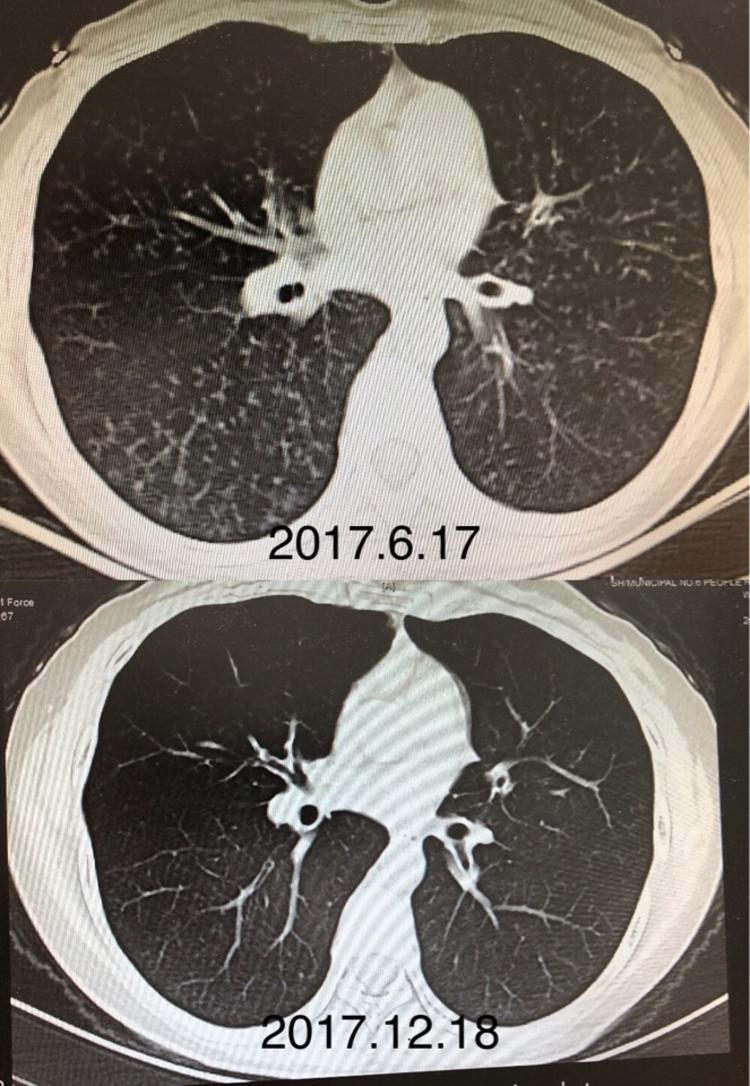

2017年6月胸部ct提示双肺弥漫性小结节影,散在支气管扩张.

复查ct,患者原来狭窄闭塞的支气管已经复通.